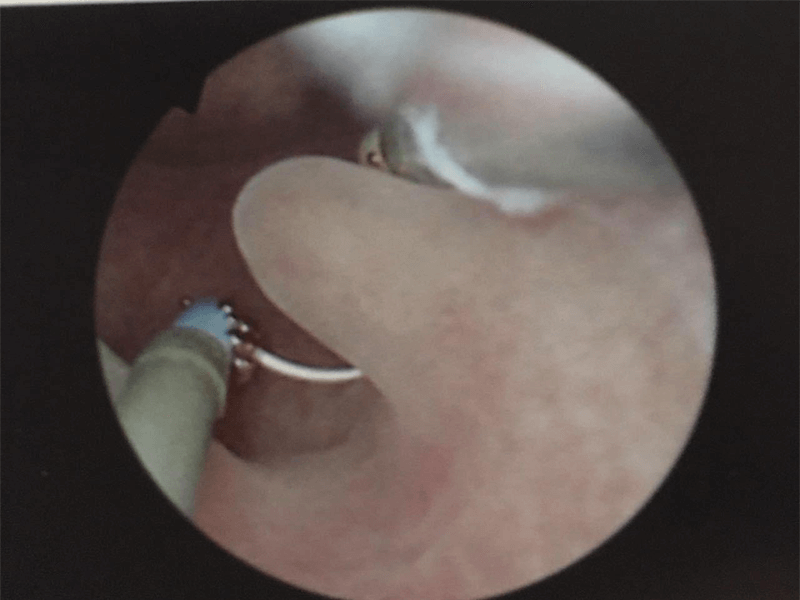

進行第三代試管嬰兒治療時,宮腔鏡是一個常見的輔助性檢查方法,通過宮腔鏡可以詳細觀察子宮內部情況,並幫助醫生判斷及解決可能影響胚胎著床和發育的問題,評估子宮內膜厚度和質量,增大試管移植的成功率。評估子宮內膜厚度和質量:子宮內膜是胚胎著床及發育所需的重要環境之一,通過宮腔鏡可以直接觀察子宮內膜的厚度和質量,確定是否適合胚胎著床;發現子宮內畸形或息肉等異常情況:有些女性可能存在子宮內畸形或者子宮內腔中的...

對於試管鮮胚移植不成功的女性來說,需要在生化妊娠後宮腔鏡或者免疫全套檢查,因為利用這兩項檢查可以檢查宮腔內部環境是否存在異常、子宮內膜是否存在粘連或其他不良情況,另外,在檢查後不僅可以找出鮮胚移植失敗的原因,還可以對症治療,避免下一次移植失敗,提高二次移植的試管成功率。宮腔鏡檢查就是利用宮腔鏡檢視患者子宮腔內的情況,並對宮腔內疾病進行診斷和治療,還可以清晰的觀察到宮腔內的各種改變,免疫全套檢查主要...

通常情況下,女性在進行試管輔助生育的時候,若是三次移植都失敗了的話,此時做一個宮腔鏡檢查是非常有必要的,但是需要不要進行宮腔鏡手術是要根據自己的子宮狀態決定的,不是每個人都必須做,只有患者子宮有異常狀態的時候才用做,比如子宮出血、內膜息肉等。宮腔鏡手術是指用宮腔鏡來進行的微創手術,一般是在患者月經乾淨後的早卵泡期進行該項手術,手術時長很短,通常一個小時就可以完成,該項技術在試管嬰兒中也被廣泛使用,...

試管嬰兒移植手術前要做宮腔鏡檢查的原因有很多,如觀察子宮形態是否適合孕育胎兒以及觀察子宮內是否有不利於胚胎髮育成長的因素等等,若是有的話就需要先進行治療,以使其恢復正常,以免影響移植後胚胎著床成功率,當然大家在做該項檢查之前,一定要注意在月經乾淨後1周視為比較適宜的時間,其原因就是此時子宮內膜處於增值早期,檢查時不宜出現出血狀態。試管移植前做宮腔鏡檢查原因就目前來說,宮腔鏡檢查是比較常用的婦科檢查...

試管正式移植前不一定要做預移植和宮腔鏡,所以如果在取卵之後沒有做這兩項檢查,也是可以直接移植胚胎的,如果是移植鮮胚,三天左右就可以移植,如果是移植的凍胚,那麼要等到下個月或者合適的時機才可以移植,另外,無論在正式移植之前做不做預移植和宮腔鏡,都要進行內膜和卵泡監測,確定移植胚胎的具體時間。預移植就是非正式的移植,就是按照正式移植的方法預先模擬胚胎移植的全過程,宮腔鏡是一項微創手術,主要是對子宮肌瘤...